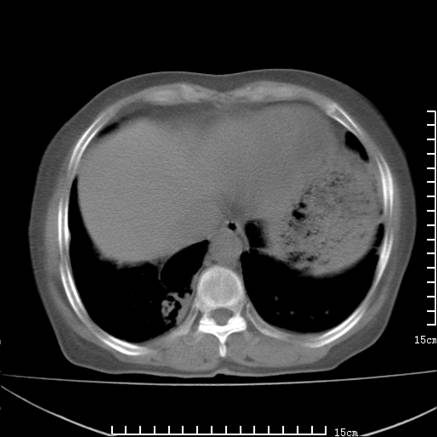

女,王某,58岁,咳嗽三个月余,基层医院二个月前诊为肺结核,用抗结核药二个月无明显疗效。

心包积液致肺瘀血.右侧周围型肺癌伴肺内转移,中间裂积液,叶间胸膜肥厚.右上肺大泡,右侧胸膜肥厚.

双肺继发型tb,心功能不全并肺淤血、心包、双侧叶间裂积液,肺大泡,右下胸膜肥厚钙化。